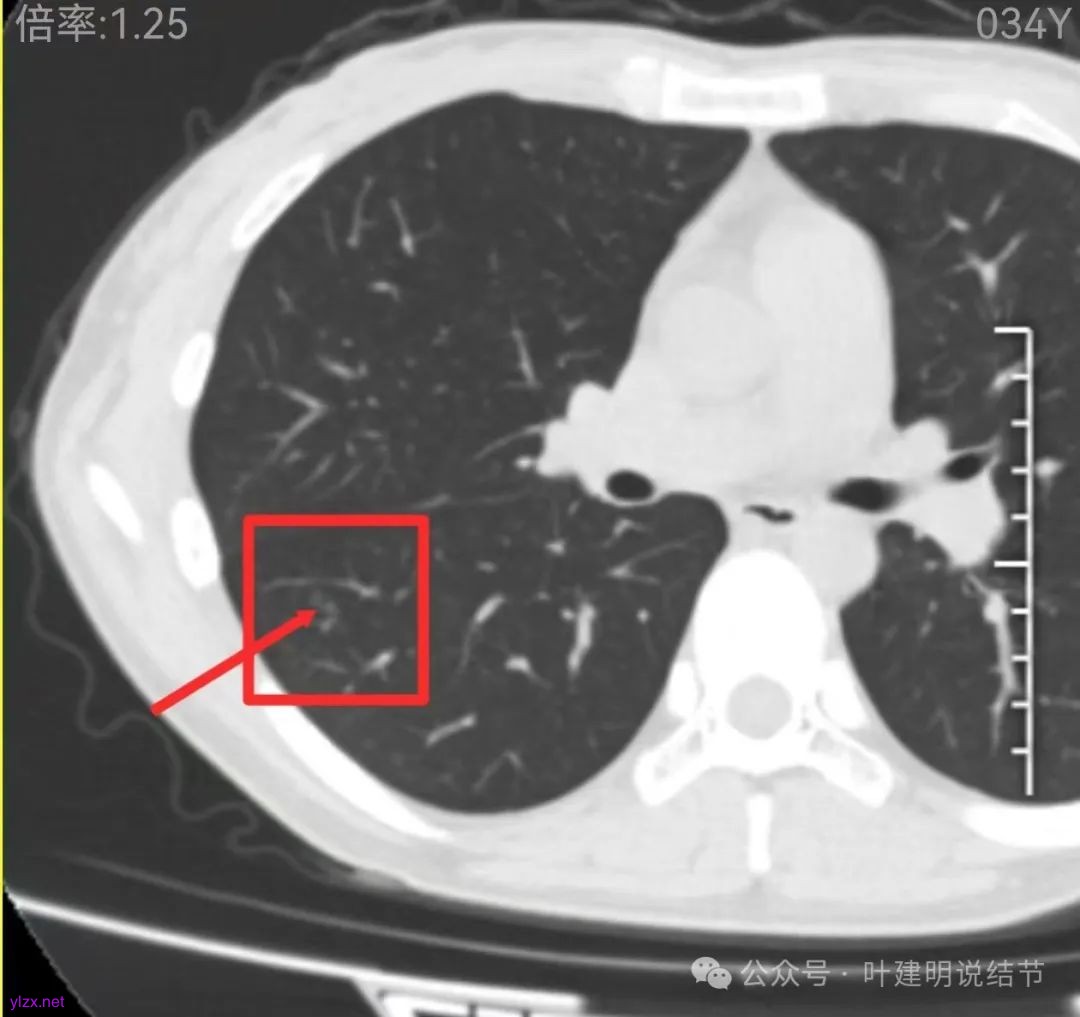

先来看2024年12月的影像:

右下叶磨玻璃结节伴空泡征,轮廓较清,瘤肺边界清楚。

表面不平,轮廓较清,有血管进入,边缘略显毛糙。

病灶内有少许偏实性成分,与血管关系较为密切,局部似有浅分叶的样子。